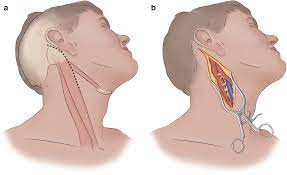

Value added benefits of the Minimally Invasive Surgery with Carotid Endarterectomy: